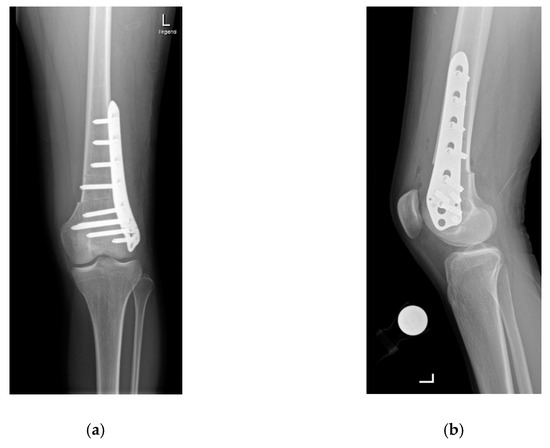

A lateral subvastus approach is used for the supracondylar osteotomies [1,7,12]. Two Kirschner wires are placed anteriorly 3–5 cm above the metaphysis to monitor the planned angle of correction. The osteotomy is performed horizontally with an oscillating saw and then the distal femur is externally rotated to correct the increased internal rotation until the two Kirschner wires are positioned as the preoperative planning has indicated. Fixation of the osteotomy is performed using a locking screw osteosynthesis plate (Figure 2a,b).

Figure 2.

Anteroposterior (a) and sagittal (b) radiographs showing the situation after supracondylar rotational osteotomy.